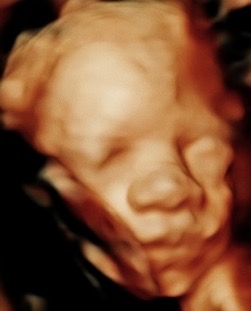

Hi, my name is Crystal Heller, and I’m the owner of Miracle 3D Moments. For the past five years, I’ve had the privilege of helping moms, dads, and families see and bond with their babies before they’re born. It’s been the most rewarding part of my life watching the smiles, the tears of joy, and the comfort that comes when a mom-to-be sees her little one moving, yawning, and even smiling.